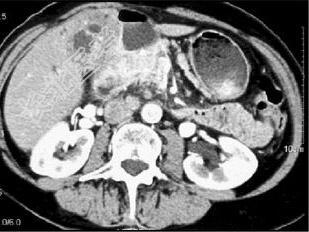

- 单项选择题患者70岁,体重减轻, 结合图像,最可能的诊断是 ( )

A、黑色素瘤转移

B、结肠癌转移

C、肝癌

D、胆囊癌

E、以上都不是